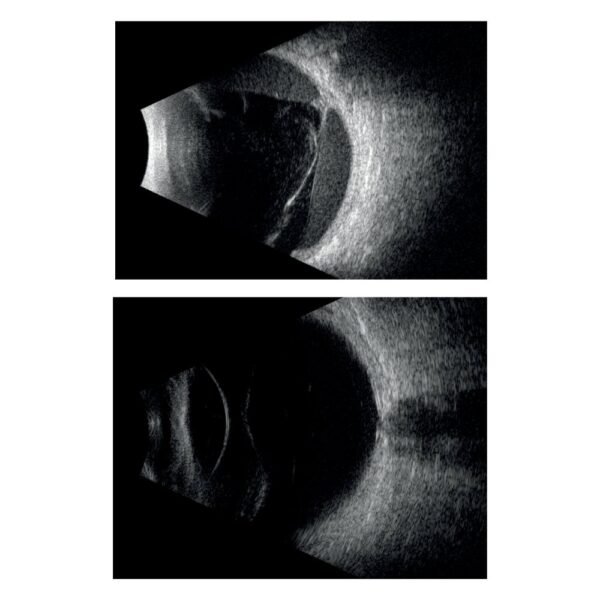

A Quantel Medical, líder mundial em ultrassom ocular, apresenta sua nova plataforma modular de ultrassom A/B/S/UBM, o ABSolu. Esta nova plataforma oferece uma qualidade de imagem excepcional através da sua nova interface ergonômica e design moderno.